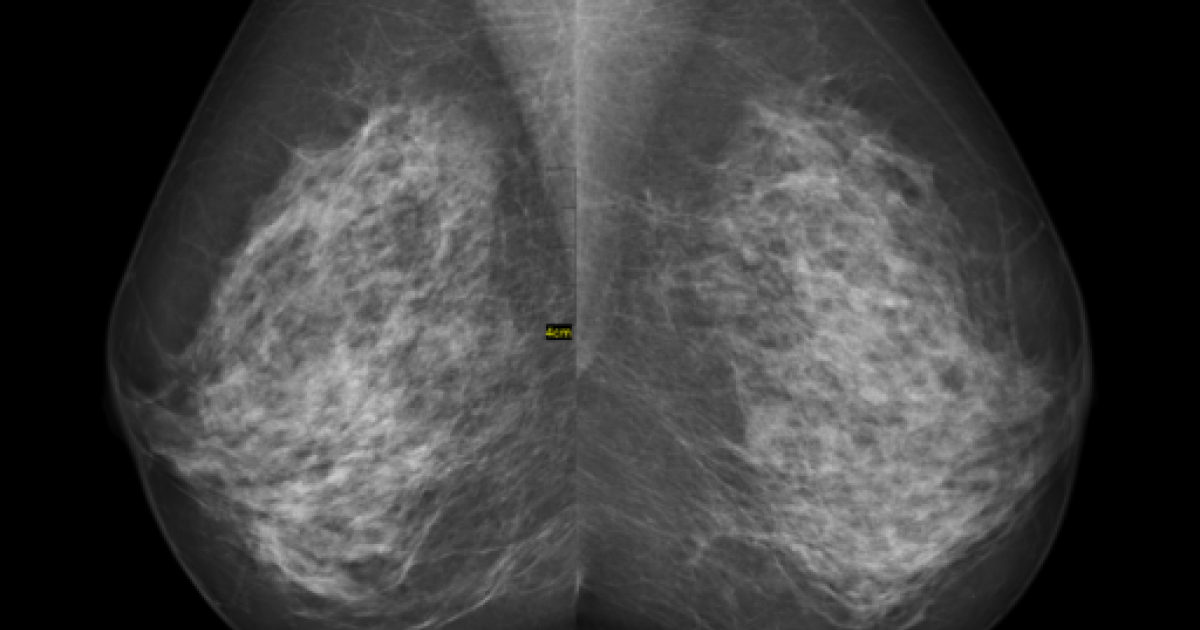

Mammography remains the standard means of screening for breast cancer. For women with denser breast tissue, the superimposition of tissue may mask early tumors even for the most observant of radiologists. A majority of states require the specific disclosure of breast density and the attendant possibility of falsely negative reports to patients. A study in Radiology takes a focused look at these patients using an automated measure of breast density rather than the subjective measures used in the US.

Volumetric breast density was automatically calculated by the imaging software is analogous to the BI-RADS classification used in the US and had been shown previously to correlated “moderately” with BI-RADS. For this study, the two least dense groups were labeled “non-dense,” and the two higher categories of breast density were labeled “dense” breasts.

- 28% of women were identified as having dense breasts.